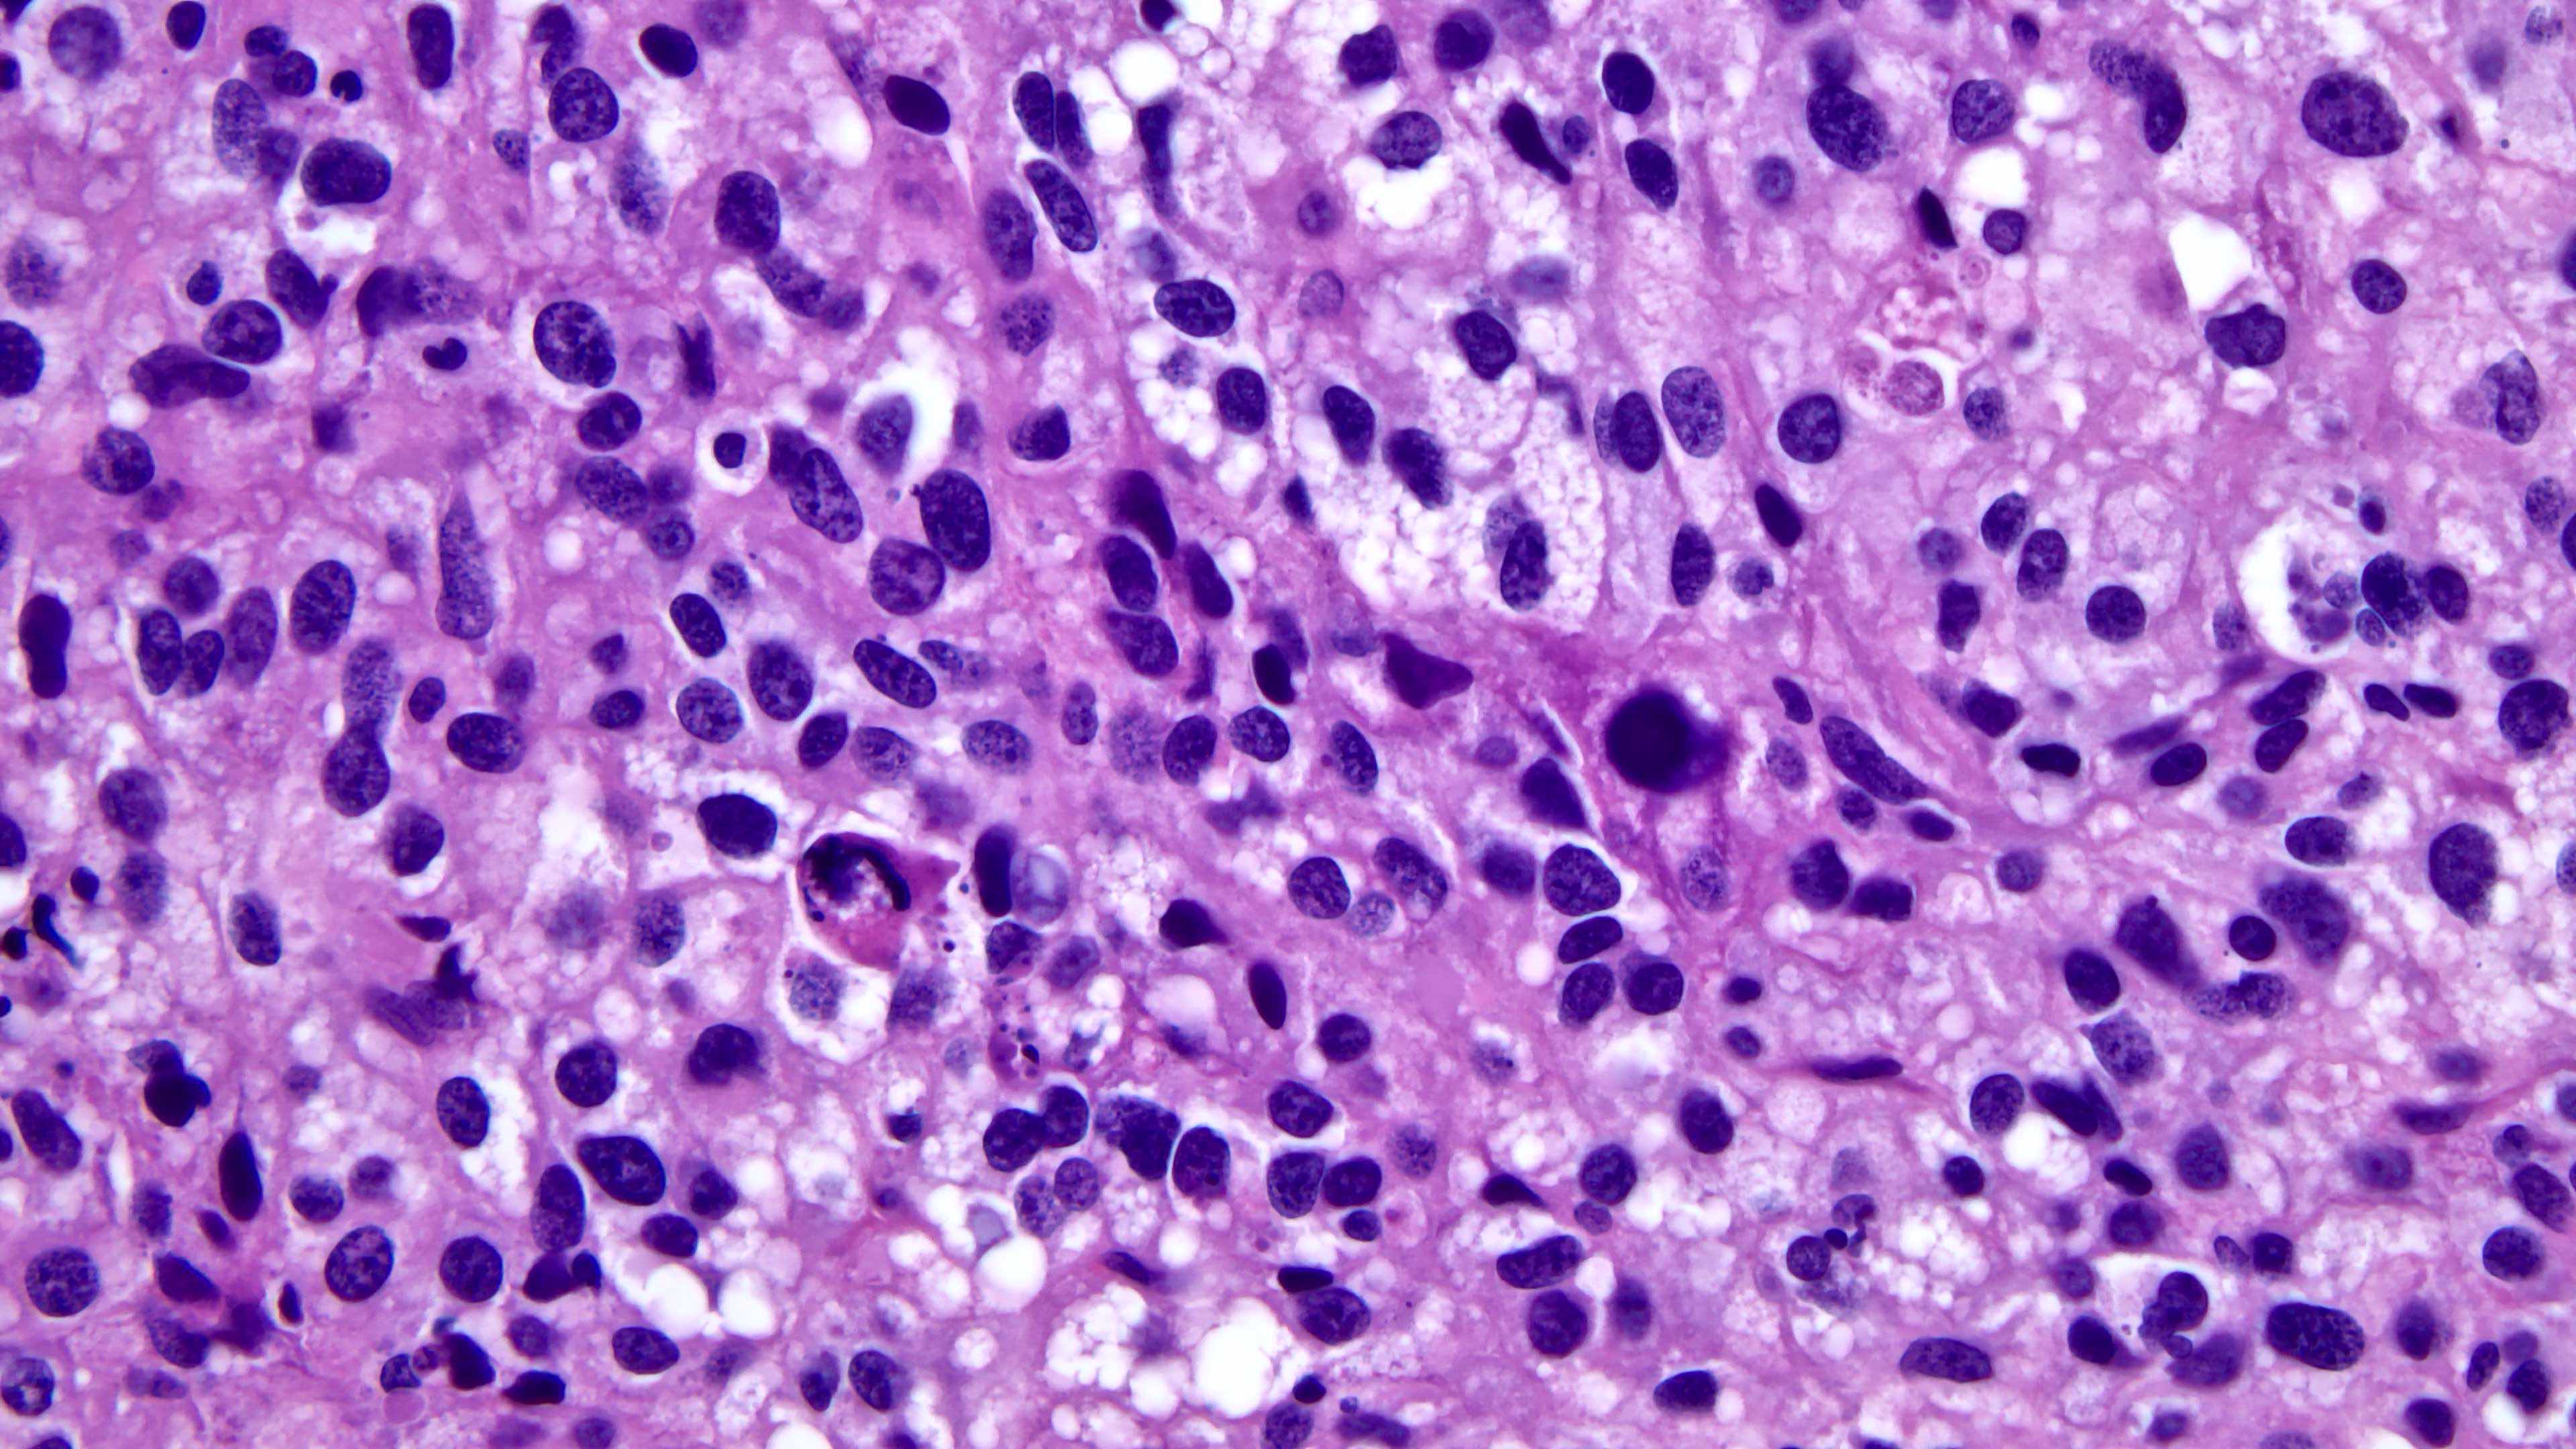

Pleomorphic

Abnormal cells